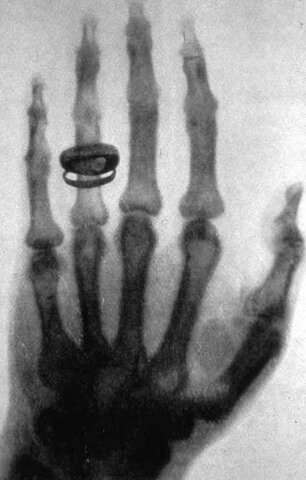

• Rayos x

Rayos x

Los rayos X fueron descubiertos en Hamburgo, Alemania en 1895 por Wilhelm Konrad Renten después de un experimento accidental con rayos catódicos.